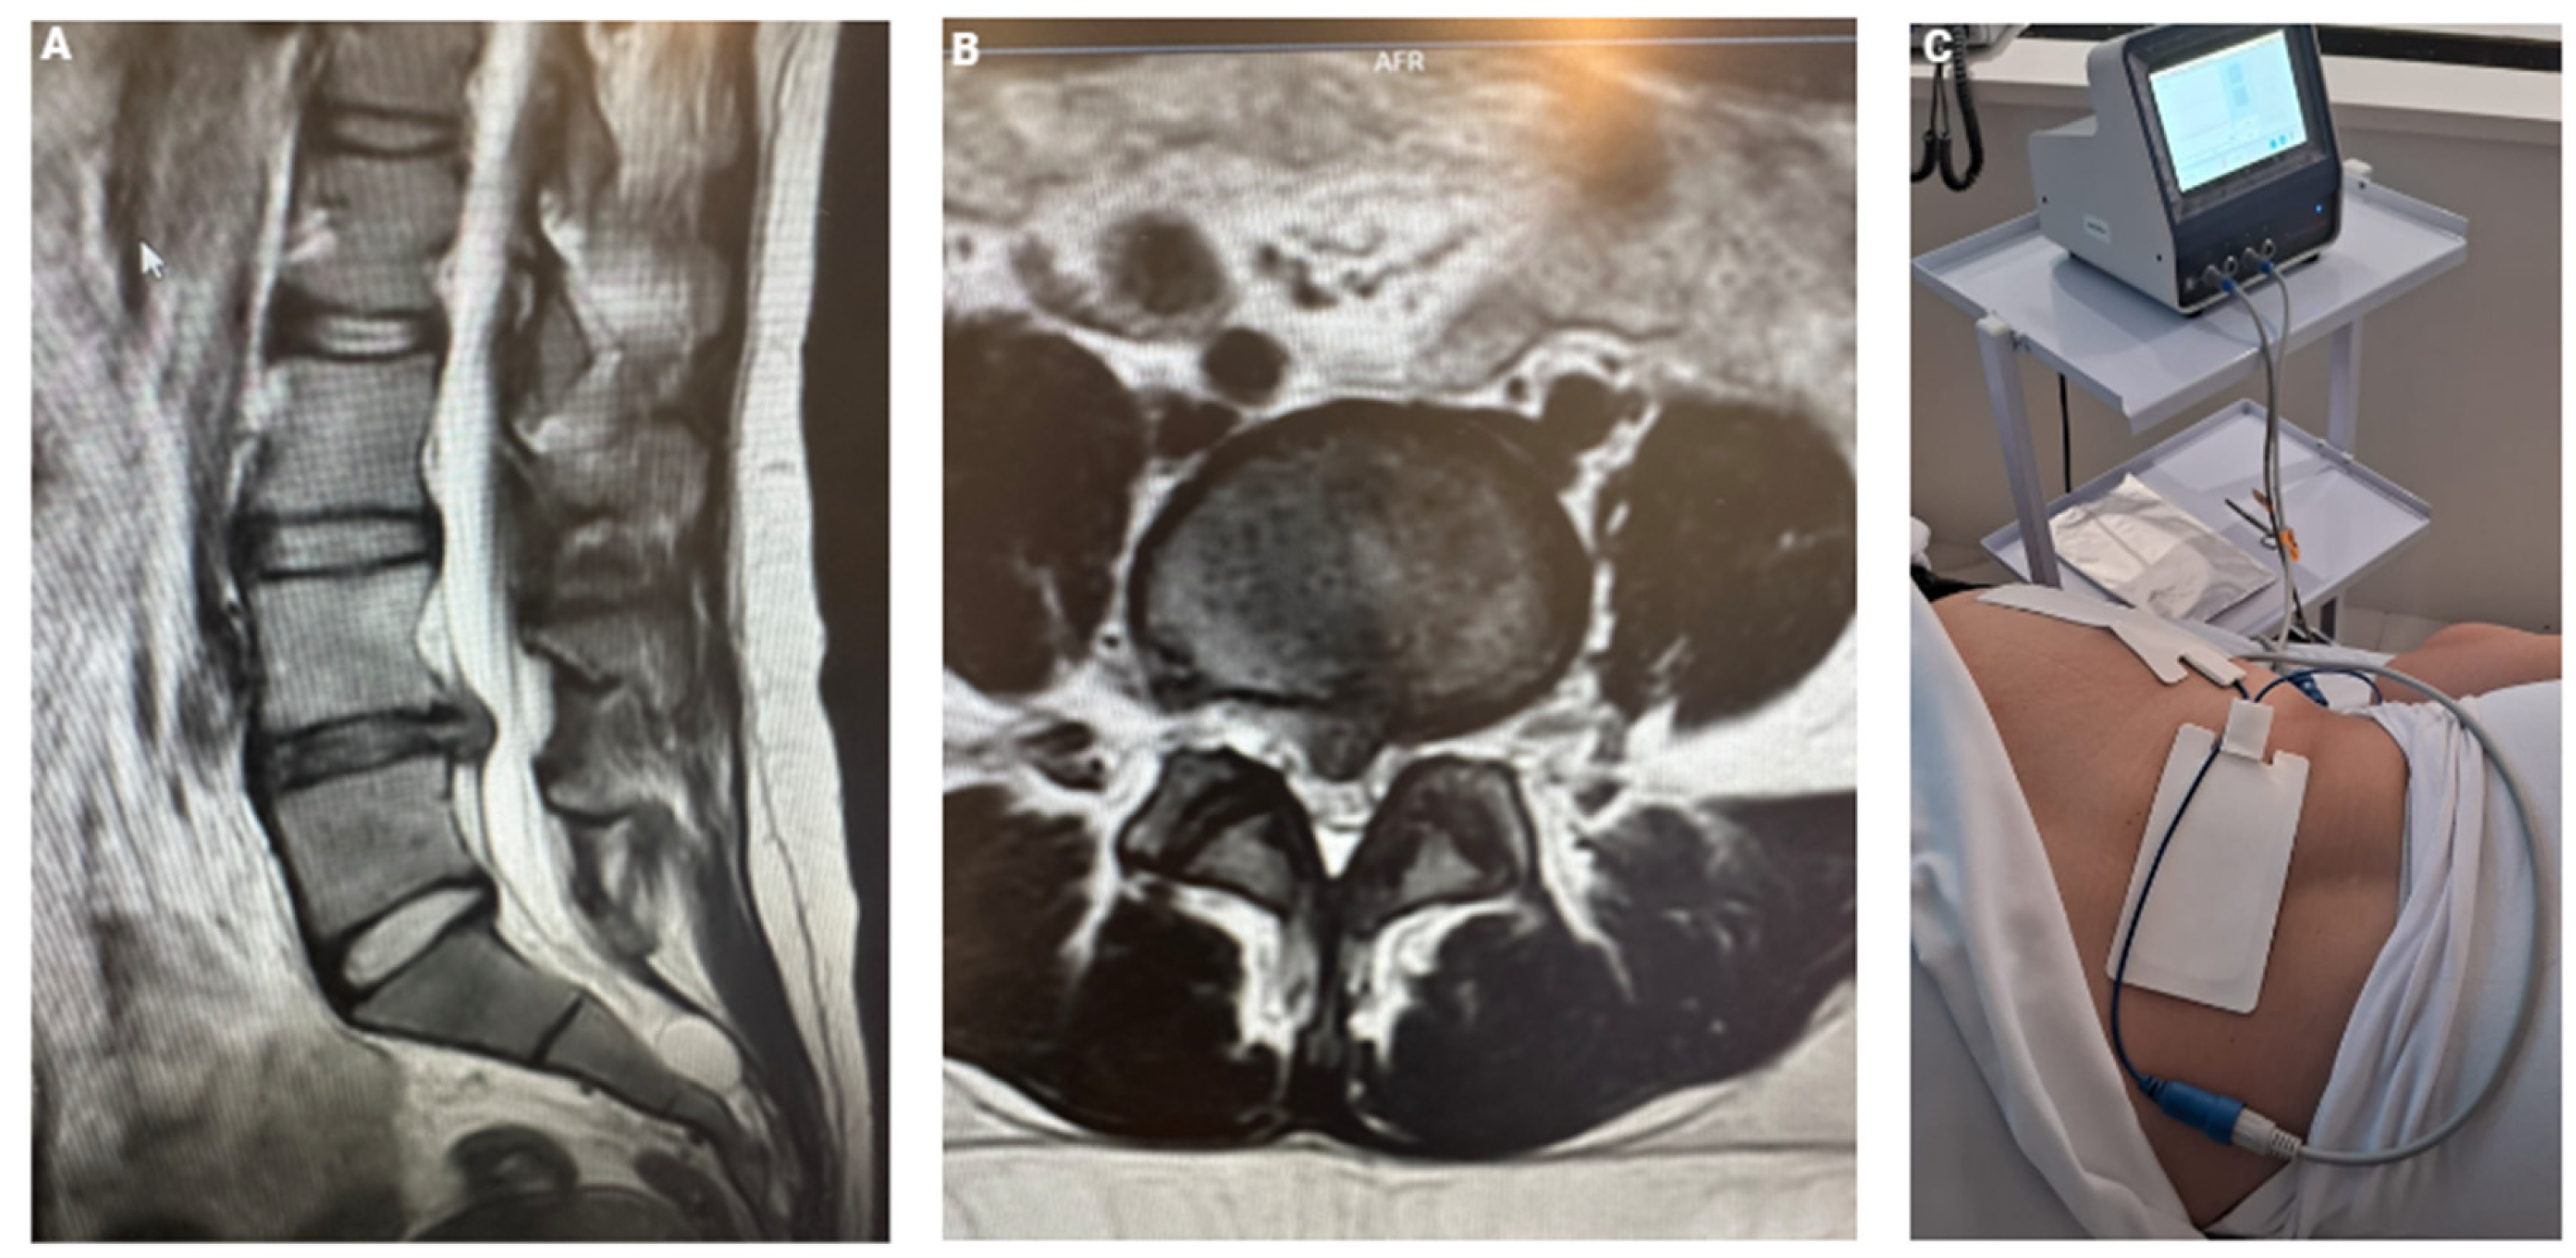

After 24 months, the patient returned to our clinic with mild recurrence of pain, localized to the gluteal region without any radiation. Regardless, she still continued to engage in her usual sports activities without claudication or limitations. A new MRI (Figure 2) revealed significant improvement compared to the previous scan, showing the L5-S1 disc in better condition, though some early signs of degeneration were present in the L4-5 intervertebral disc. While this type of imaging progression is expected due to the natural course of the disease, it is noteworthy that she remained symptom-free and clinically stable for an extended period.

Figure 2. Recent Nuclear Magnetic Resonance Imaging demonstrating good evolution of herniated disc L5-S1.